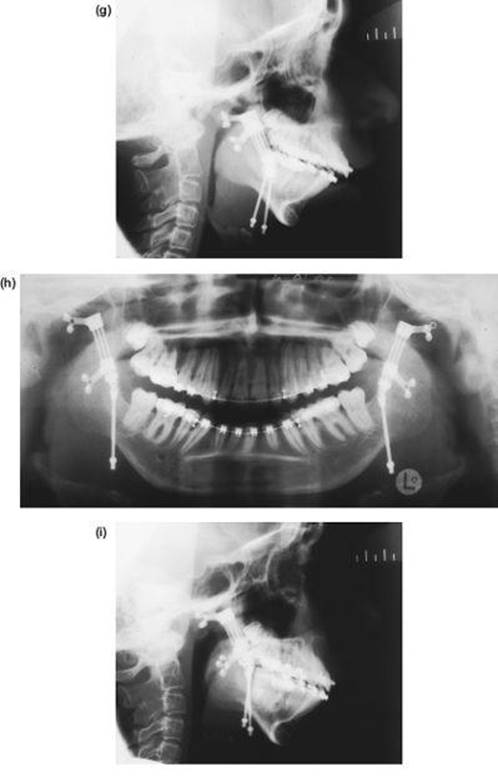

The Inverted L Osteotomy

Indications

This operation is valuable when there is a need to increase both the ramus height and body length at the same time, especially when the sagittal split osteotomy is not possible. Such cases are usually gross congenital mandibular hypoplasia or, occasionally, acquired hypoplasia following condylar fractures or when previous surgery has disturbed the bony anatomy. The operation differs in concept from the sagittal split procedure in that a bone graft is inserted to make up the deficiency.

Technique

1. The surgical approach is exactly the same as for the extraoral subsigmoid osteotomy (steps 1-6 and see Figure 9.4) except that the bone cut is made from the anterior border of the ascending ramus, passing distally, to behind the estimated position of the lingula then downwards to the lower border anterior to the angle, i.e. to the antegonial notch (Figure 9.7a).

2. With bilateral deformities the approach is repeated on the opposite side.

3. The mandible is then temporarily fixed into occlusion. Where the maxilla is normal this presents no problems. However, if there is a deformity of the maxilla this must be corrected before the inverted L and fixed with bone plates.

Mobilising the small mandible into the desired anterior position can be difficult and is facilitated by drilling a hole bilaterally in the lower border of the mandible just anterior to the osteotomy cut and passing a 0.5 mm traction wire to be attached to heavy forceps. When anterior traction is applied, explore the deep tissues medial to the mandible with a finger to find any restraining bands of periosteum, muscle or ligament. These must be vigorously divided with the finger to ensure stability.

4. With the proximal condylar fragment confirmed to be in the fossa, the gap created can be measured, and a template formed with sterile paper or card.

Figure 9.7 (a), (b)

5. An interpositional graft is now obtained. The ideal source is cortico-cancellous bone from the iliac crest. A solid cancellous graft can be used but the incorporation of one cortex provides reassuring stability. Some surgeons use split rib for the gap. Two miniature bone plates provide excellent rigidity and form (Figure 9.7b).